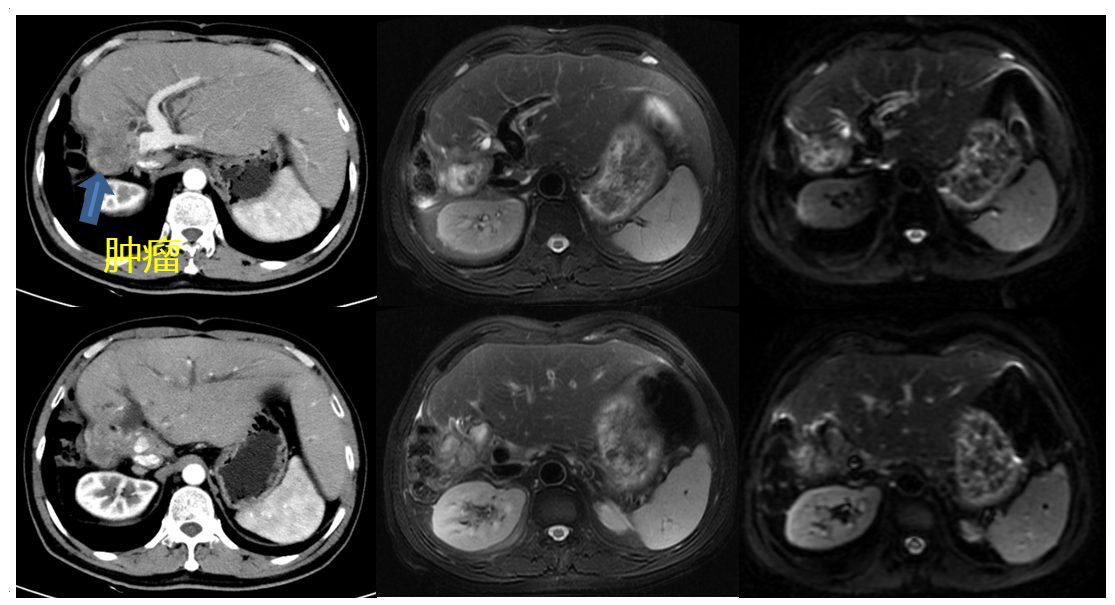

2016年10月因黄疸再次入院。入院后CT和MRI提示胆管癌胆肠吻合口复发,伴肝门部区域淋巴结转移(图1);CA199 >12000 U/L;临床诊断为Ⅲc期(T4N1M0)。

图1. 2016年11月CT和MRI检查

2016年11月4日行“肝左内叶+左尾页切除+肝门部胆管切除+门静脉重建+下腔静脉壁部分切除重建+膈肌部分切除修补+LN8/13/16淋巴结清扫+胆肠吻合拆除重建术”。术后病理示中低分化腺癌伴淋巴结转移,胆管切缘阴性,肝门部淋巴结1/6枚见癌转移,pT4N1M0。